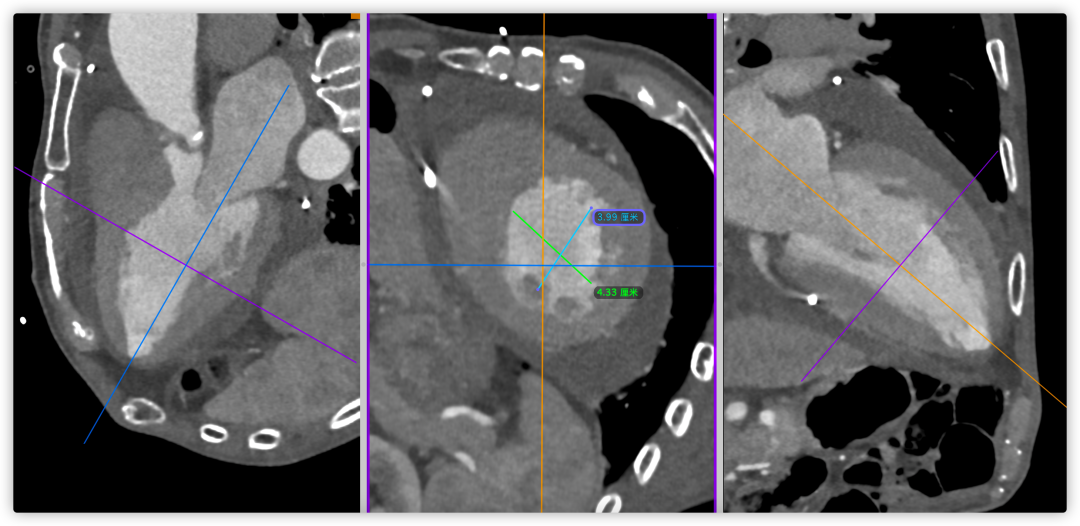

主动脉根部CT断层

根部角度/瓣环/左室流出道

瓣上结构2,4,6,8,10,12mm

SOV/STJ/AAO

左冠风险评估